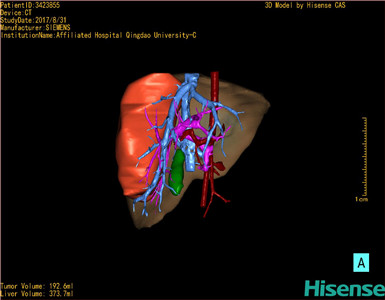

将0.625mm双源薄层CT资料的静脉期和动脉期Dicom格式文件导入海信CAS系统。

通过调节窗宽窗位调整CT序号,对肝实质,胆囊,下腔静脉,肿瘤,肝动脉、门静脉及肝静脉等进行三维重建;系统自动计算肝脏体积。

模拟手术操作,自动计算切除肿瘤体积。肝脏体积为373.7ml,肿瘤体积是192.6ml,是肝脏体积的0.5倍,通过比对2-3岁正常肝脏体积为475.97±99.7ml,通过术前模拟手术,精准判断切除后剩余肝脏体积能耐受,避免肝衰竭发生。

术前三维重建:

重建图片